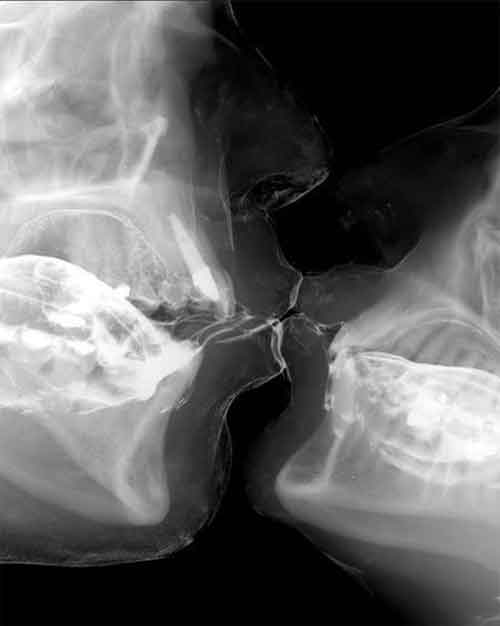

In alcuni casi i declamati effetti positivi del bacio sono stati confermati da valide ricerche scientifiche. E’ questo il caso della sua azione antistress, dimostrati da un piccolo studio condotto nel 2009 dai ricercatori del College Lafayette (Stati Uniti). Gli scienziati hanno misurato i livelli di ossitocina – l’ormone del benessere e della socialità – e quelli di cortisolo – l’ormone dello stress – prima e dopo un bacio. E’ stato, così, scoperto che questo gesto fa diminuire i livelli di cortisolo sia nelle donne, sia negli uomini.

Il suo effetto è molto più accentuato rispetto a quello scatenato dal tenersi per mano, ma secondo gli esperti è significativo solo se ci si bacia spesso, mentre un unico bacio mozzafiato può provocare un effetto totalmente opposto, portando ad un aumento dell’ormone dello stress. Baci lunghi hanno, invece, un effetto sul sistema immunitario. Uno studio condotto in Giappone ha invece dimostrato che baciarsi per 30 minuti riduce i livelli delle IgE, gli anticorpi coinvolti nelle reazioni allergie.

Non sono, però, questi gli unici effetti positivi del bacio, che funziona come una vera e propria palestra per i muscoli del viso che contrasta la comparsa delle rughe d’espressione e che permette di bruciare da 2 a 6 calorie al minuto. Infine, stimolando la produzione di saliva questo gesto protegge anche i denti dall’azione nociva dei batteri, mentre lo scambio di germi che si realizza attraverso un bacio può rinforzare l’immunità. Attenzione, però, a non credere che baciare il proprio partner quando è nel pieno di una malattia possa essere una vaccinazione. Piuttosto è meglio ricordare che si tratta di un modo semplice per entrare in contatto con microbi come quelli responsabili della mononucleosi, lo streptococco e l’herpes.